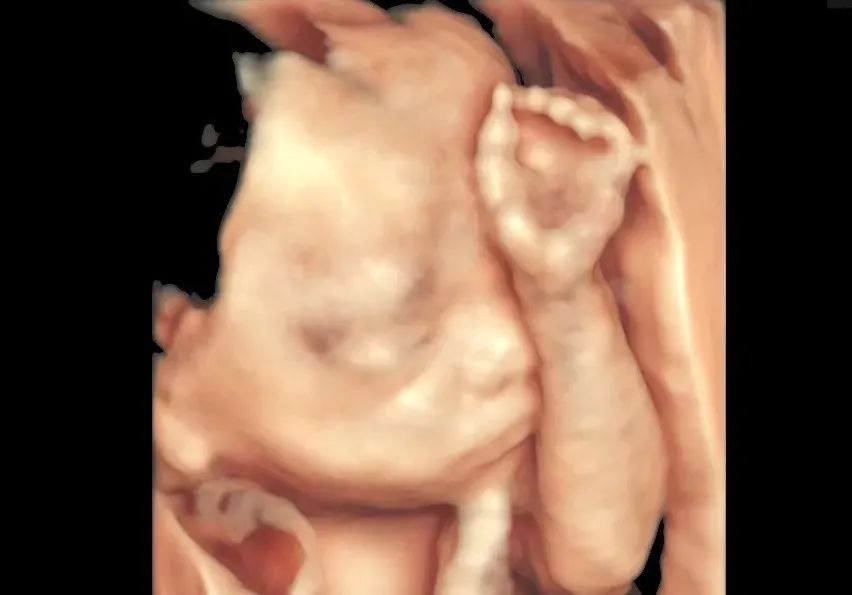

四维彩超对准妈妈来说是重要的孕期检查

产前超声筛查对她们而言其实更加重要

在和平超声门诊,我们见过很多因肚皮脂肪过厚、胎儿位置不好、超过筛查周期、羊水偏少胎儿偏大等情况而无法正常筛查的准妈妈。

这样的她们更需要超声医生的“火眼金睛”来鉴别判断胎宝宝的情况,助力胎儿健康发育成长。

个性化胎位调整 瞬见正脸

和平超声科与助产士门诊相邻,助产士会根据准妈妈自身情况,运用专业医疗手法个性化调整胎位,帮助妈妈们一次看清宝宝正脸。